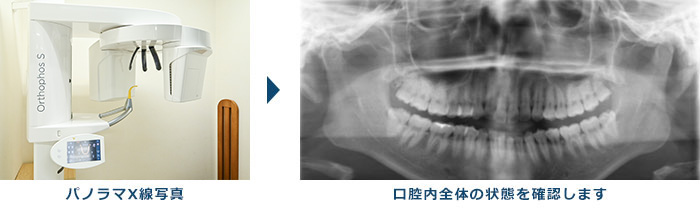

3.エックス線検査

歯周病が進行すると、歯を支えている歯槽骨が溶けてきますので、歯肉の下にある歯槽骨の高さを調べることも必要になります。歯槽骨の状態を調べるのに最も効果的な検査がエックス線検査です。エックス線検査は、歯槽骨の溶けてなくなった範囲や程度をかなり正確に知ることのできる検査になります。

当院では「SIRONA社製 ORTHOPHOS XG」というデジタルエックス線撮影機を使用しており、皆さんが気にされている撮影時の被爆量が最小限で、かつ高精細な画像が得られるように配慮しております。